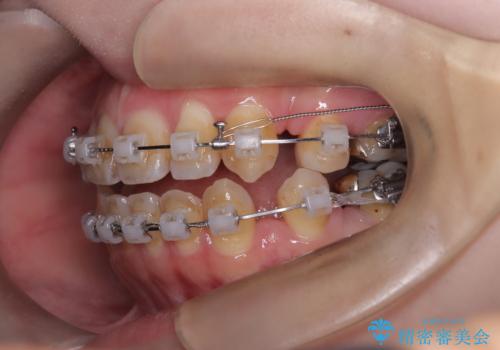

- ワイヤー矯正(クリア装置)

- 開咬と歯のデコボコ(叢生)、八重歯を主訴にご来院された患者様です。

矯正の精密検査の結果、上顎左右4番および下顎左右5番の計4本を抜歯し、ワイヤー矯正(クリア装置)にて治療を行いました。